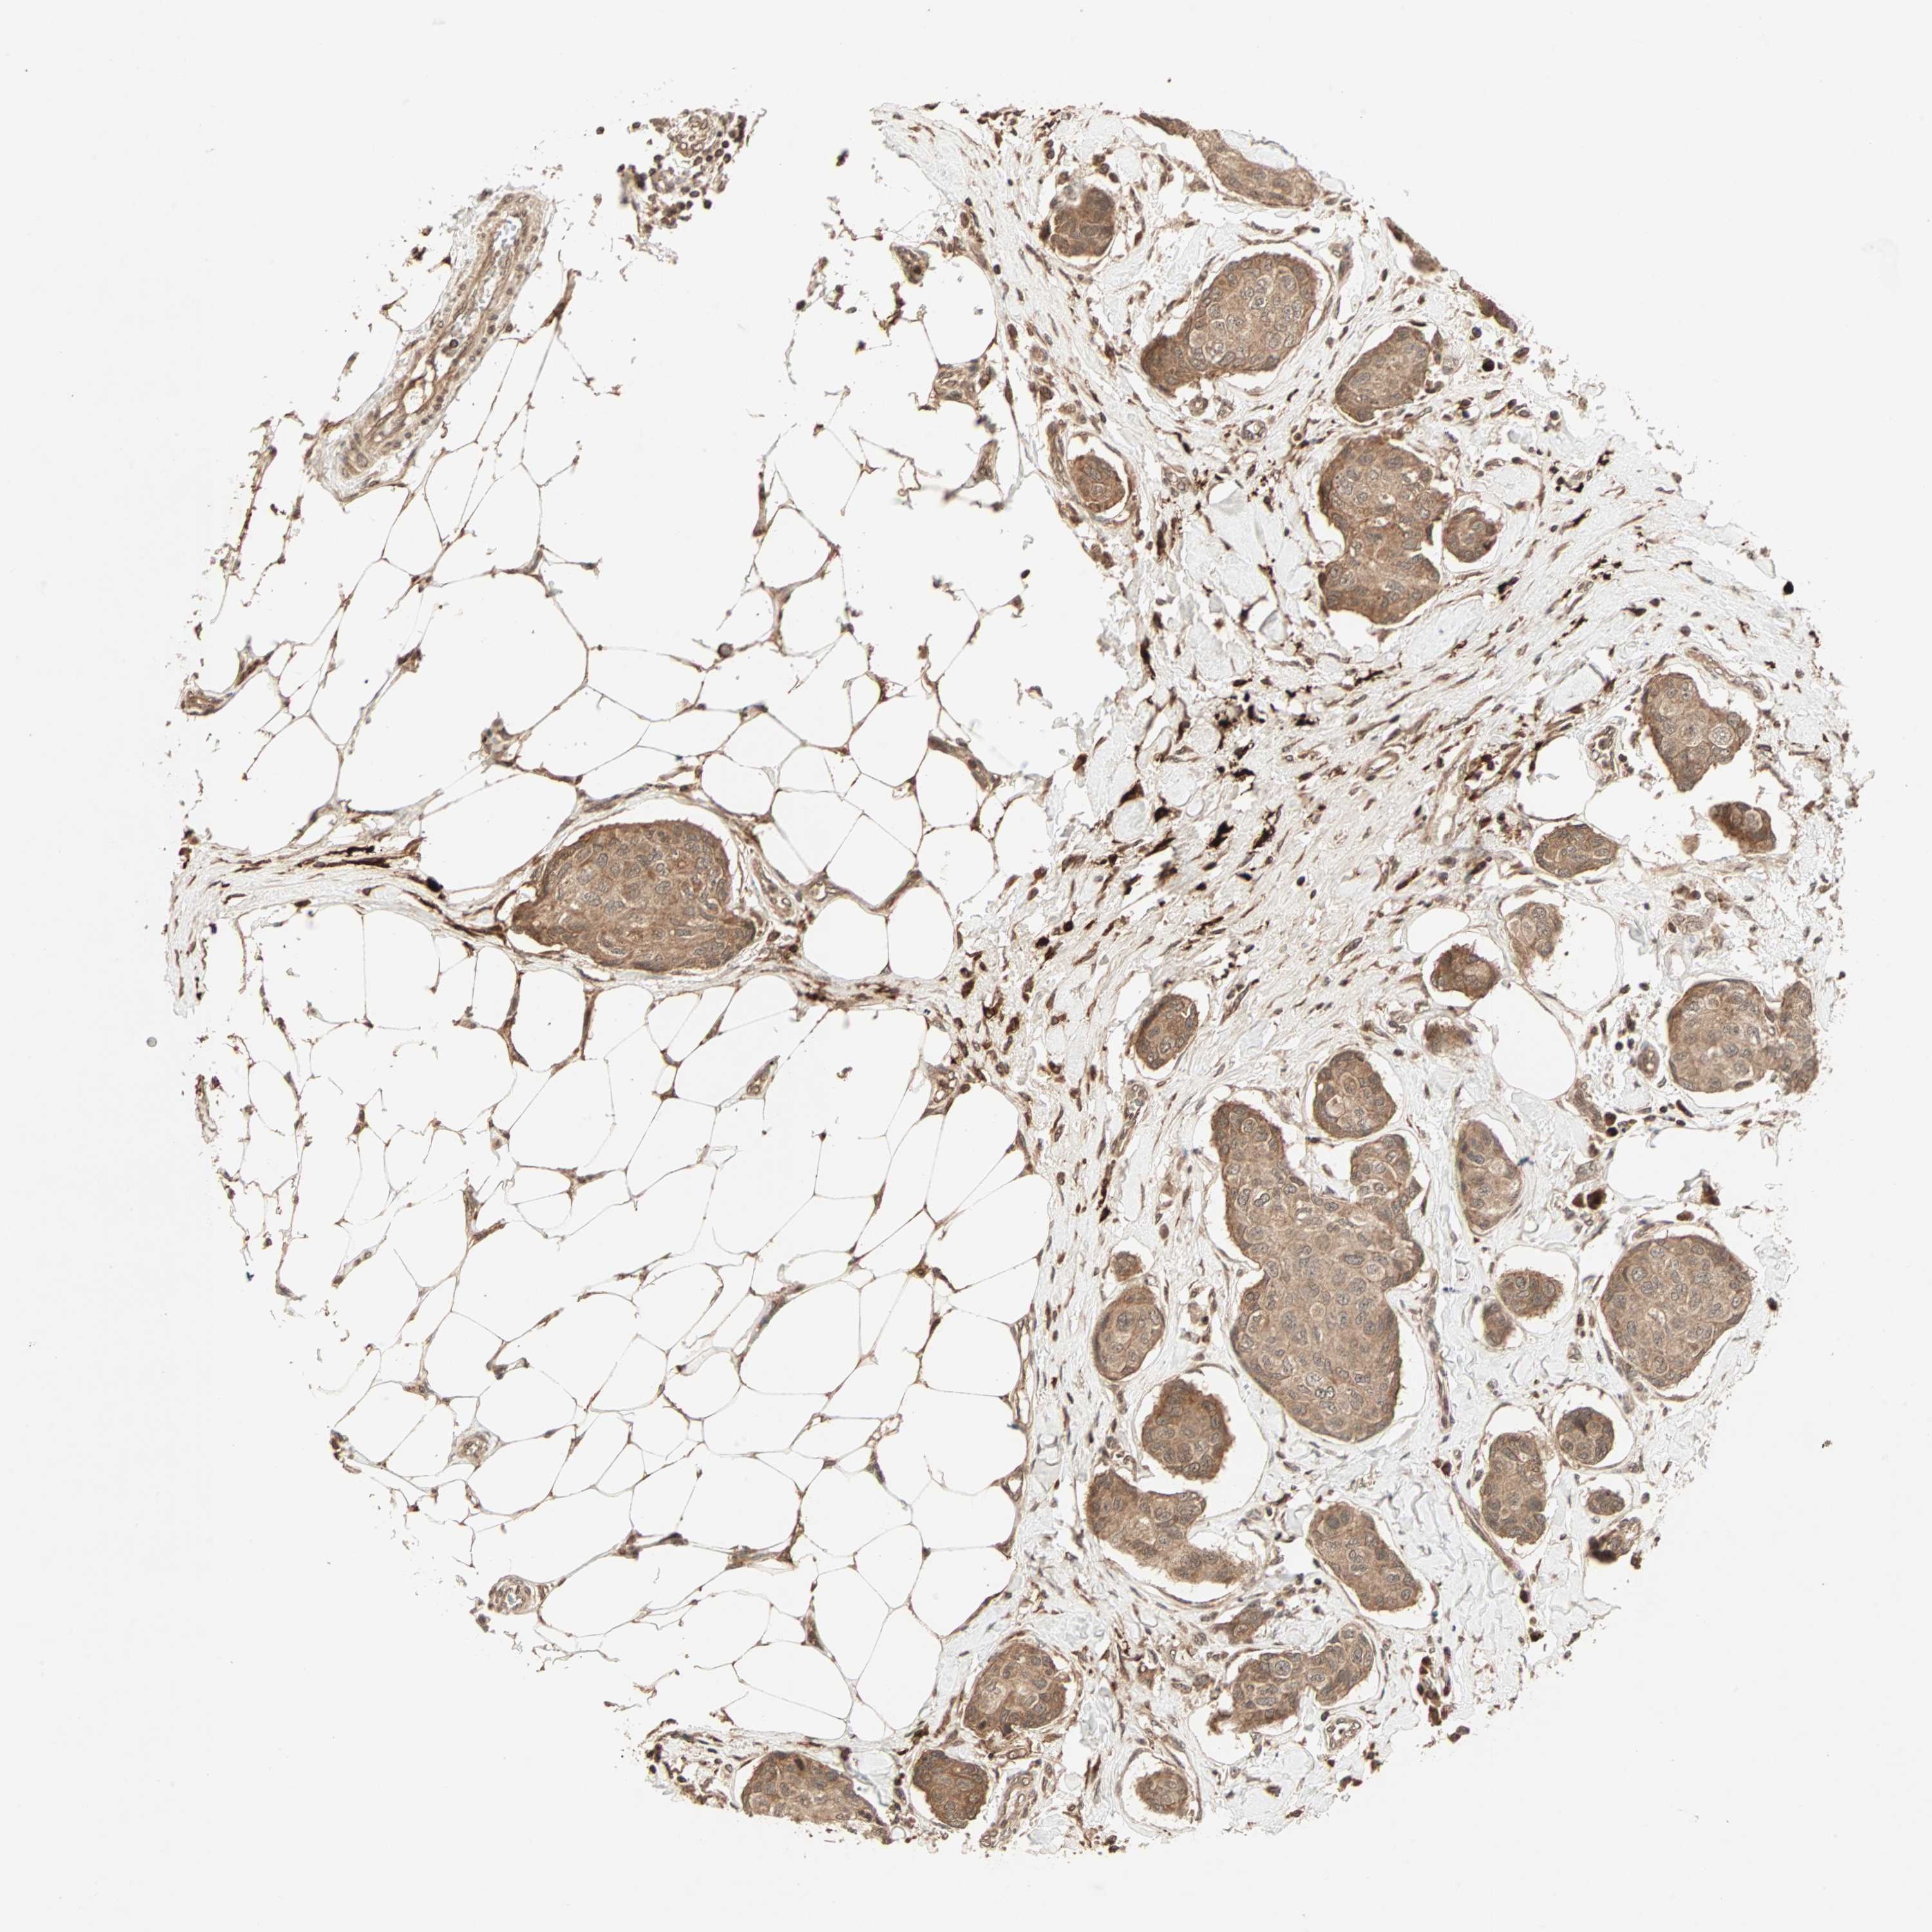

BRCA TCGA BRCA VALIDATION PROTEIN EXPRESSION

ANTIBODIES

AND

VALIDATION